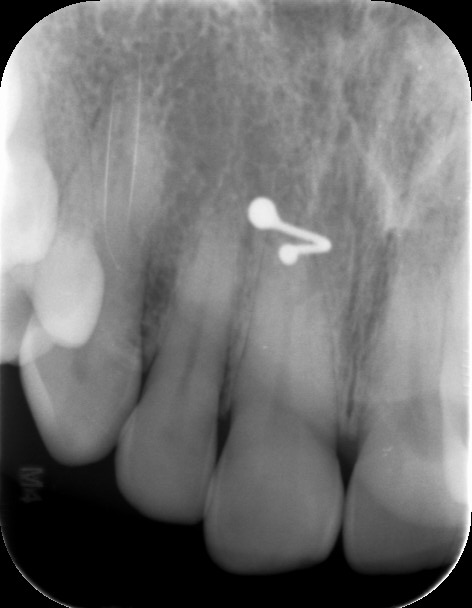

Dit zijn de foto's die ik heb

Je hebt wel een overbelasting en de wortels zijn wat kort.

Heb je een beugel gehad? Lijkt alsof er toch teveel krachten op je voortanden komen.

Je tanden kunnen inderdaad weer aan de wandel gaan na het beugelen en toch weer gaan storen in de articulatie/occlusie (dus manier van dichtbijten, schuiven enz) en dus toch overbelast raken. De overbelasting is zichtbaar als een 'verbrede parodontaal spleet' tussen je tanden en je bot. Verder zie ik toch wel een beetje botverlies, met name bij een kies waarvan de vulling overstaat. Hier blijft te veel plak en voedsel hangen. Ik zou toch eens een second opinion aanvragen bij iemand die wat meer verstand heeft van de belasting. Misschien eens terug naar de orthodontist?